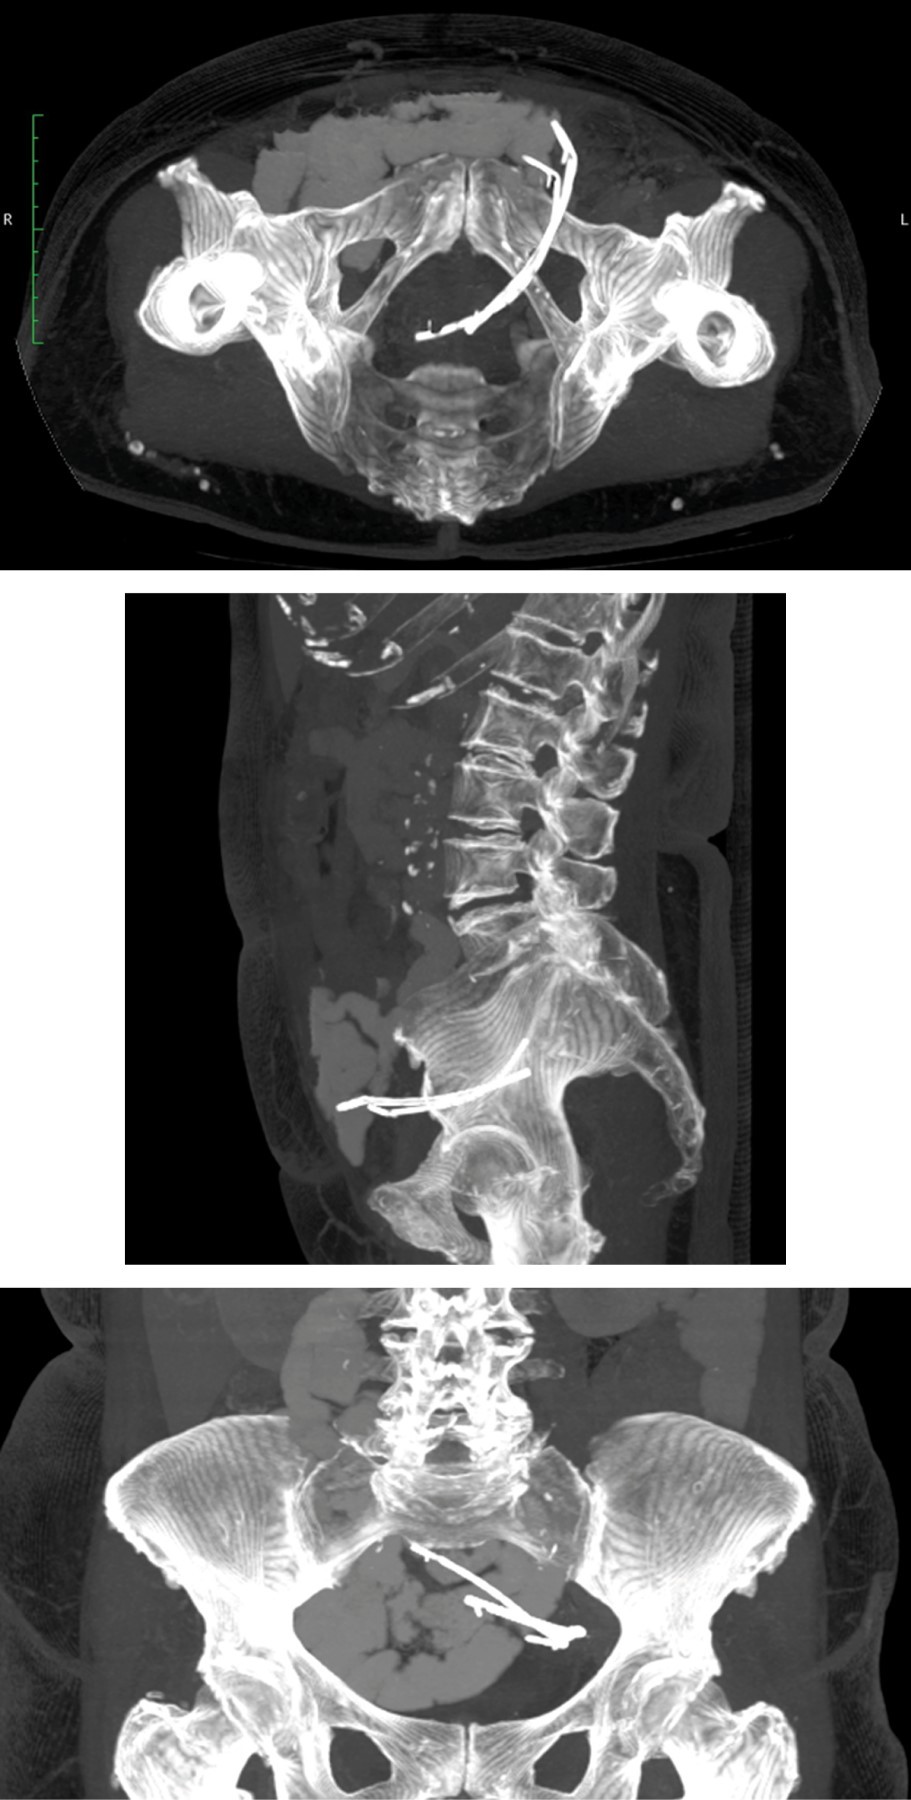

Paciente femenino de 71 años, consulta por clínica de dolor en fosa iliaca izquierda de tres meses de evolución, el cual empeora en la última semana hasta tornarse severo, por lo que acude al servicio de urgencias. Tres años antes había requerido la realización de colangiografía retrógrada endoscópica (ERCP) por coledocolitiasis, no existía claridad sobre el manejo realizado y nunca asistió a controles. A la valoración inicial, los signos vitales y estudios de laboratorio como hemograma, función renal y electrolitos eran normales; la palpación abdominal revelaba leve dolor a la palpación en fosa iliaca izquierda, sin signos de irritación peritoneal. Se realiza tomografía axial computarizada (TAC) de abdomen, que evidencia imágenes compatibles con prótesis biliares libres en cavidad pélvica (Figura 1). La colonoscopia demuestra stent enclavado en divertículo a nivel del sigmoide a los 30 cm del margen anal; dado que se encontraba atravesando la pared, se considera que la extracción endoscópica no es segura. Durante la hospitalización, presenta empeoramiento del dolor abdominal, asociado a leucocitosis y taquicardia, por lo cual es llevada a resección anterior de sigmoide por laparoscopia; se encuentran dos stents plásticos de 10 cm de longitud enclavados en la pared con comunicación directa a cavidad pélvica, asociada a formación de dos plastrones en sigmoide y unión rectosigmoide (Figura 2). Continúa hospitalizada con analgesia y manejo antibiótico por siete días y se da egreso sin complicaciones. En los cortes axial, sagital y coronal se aprecian dos imágenes alargadas compatibles con stents biliares en relación con el colon sigmoide, con extremo libre hacia la cavidad pélvica.

Figura 1